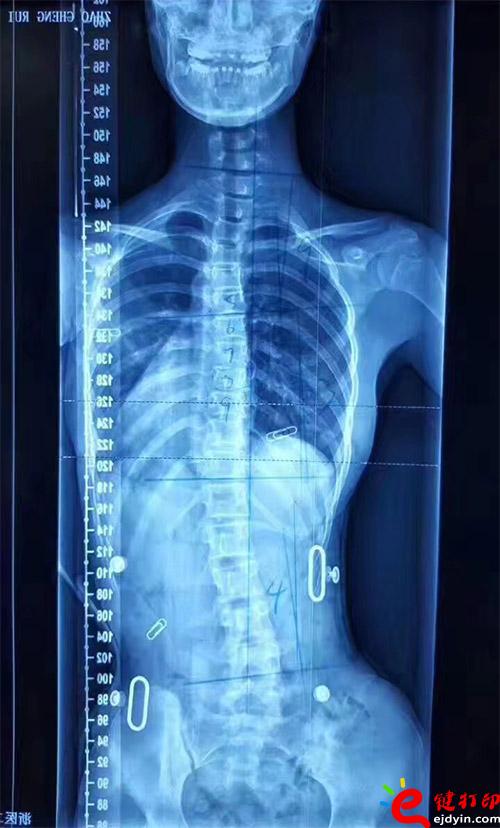

在脊柱側(cè)彎患者中,僅有10%的青少年特發(fā)性脊柱側(cè)彎患者最終需要手術(shù)治療,90%的患者可以保守治療和積極觀察。非手術(shù)治療中公認(rèn)最主要和可靠的方式是用矯形支具治療。像上圖這樣的案例就可以通過矯形器治療。每個(gè)人的畸形不一樣,就需要像3D打印這樣可定制又便宜的技術(shù)幫助。